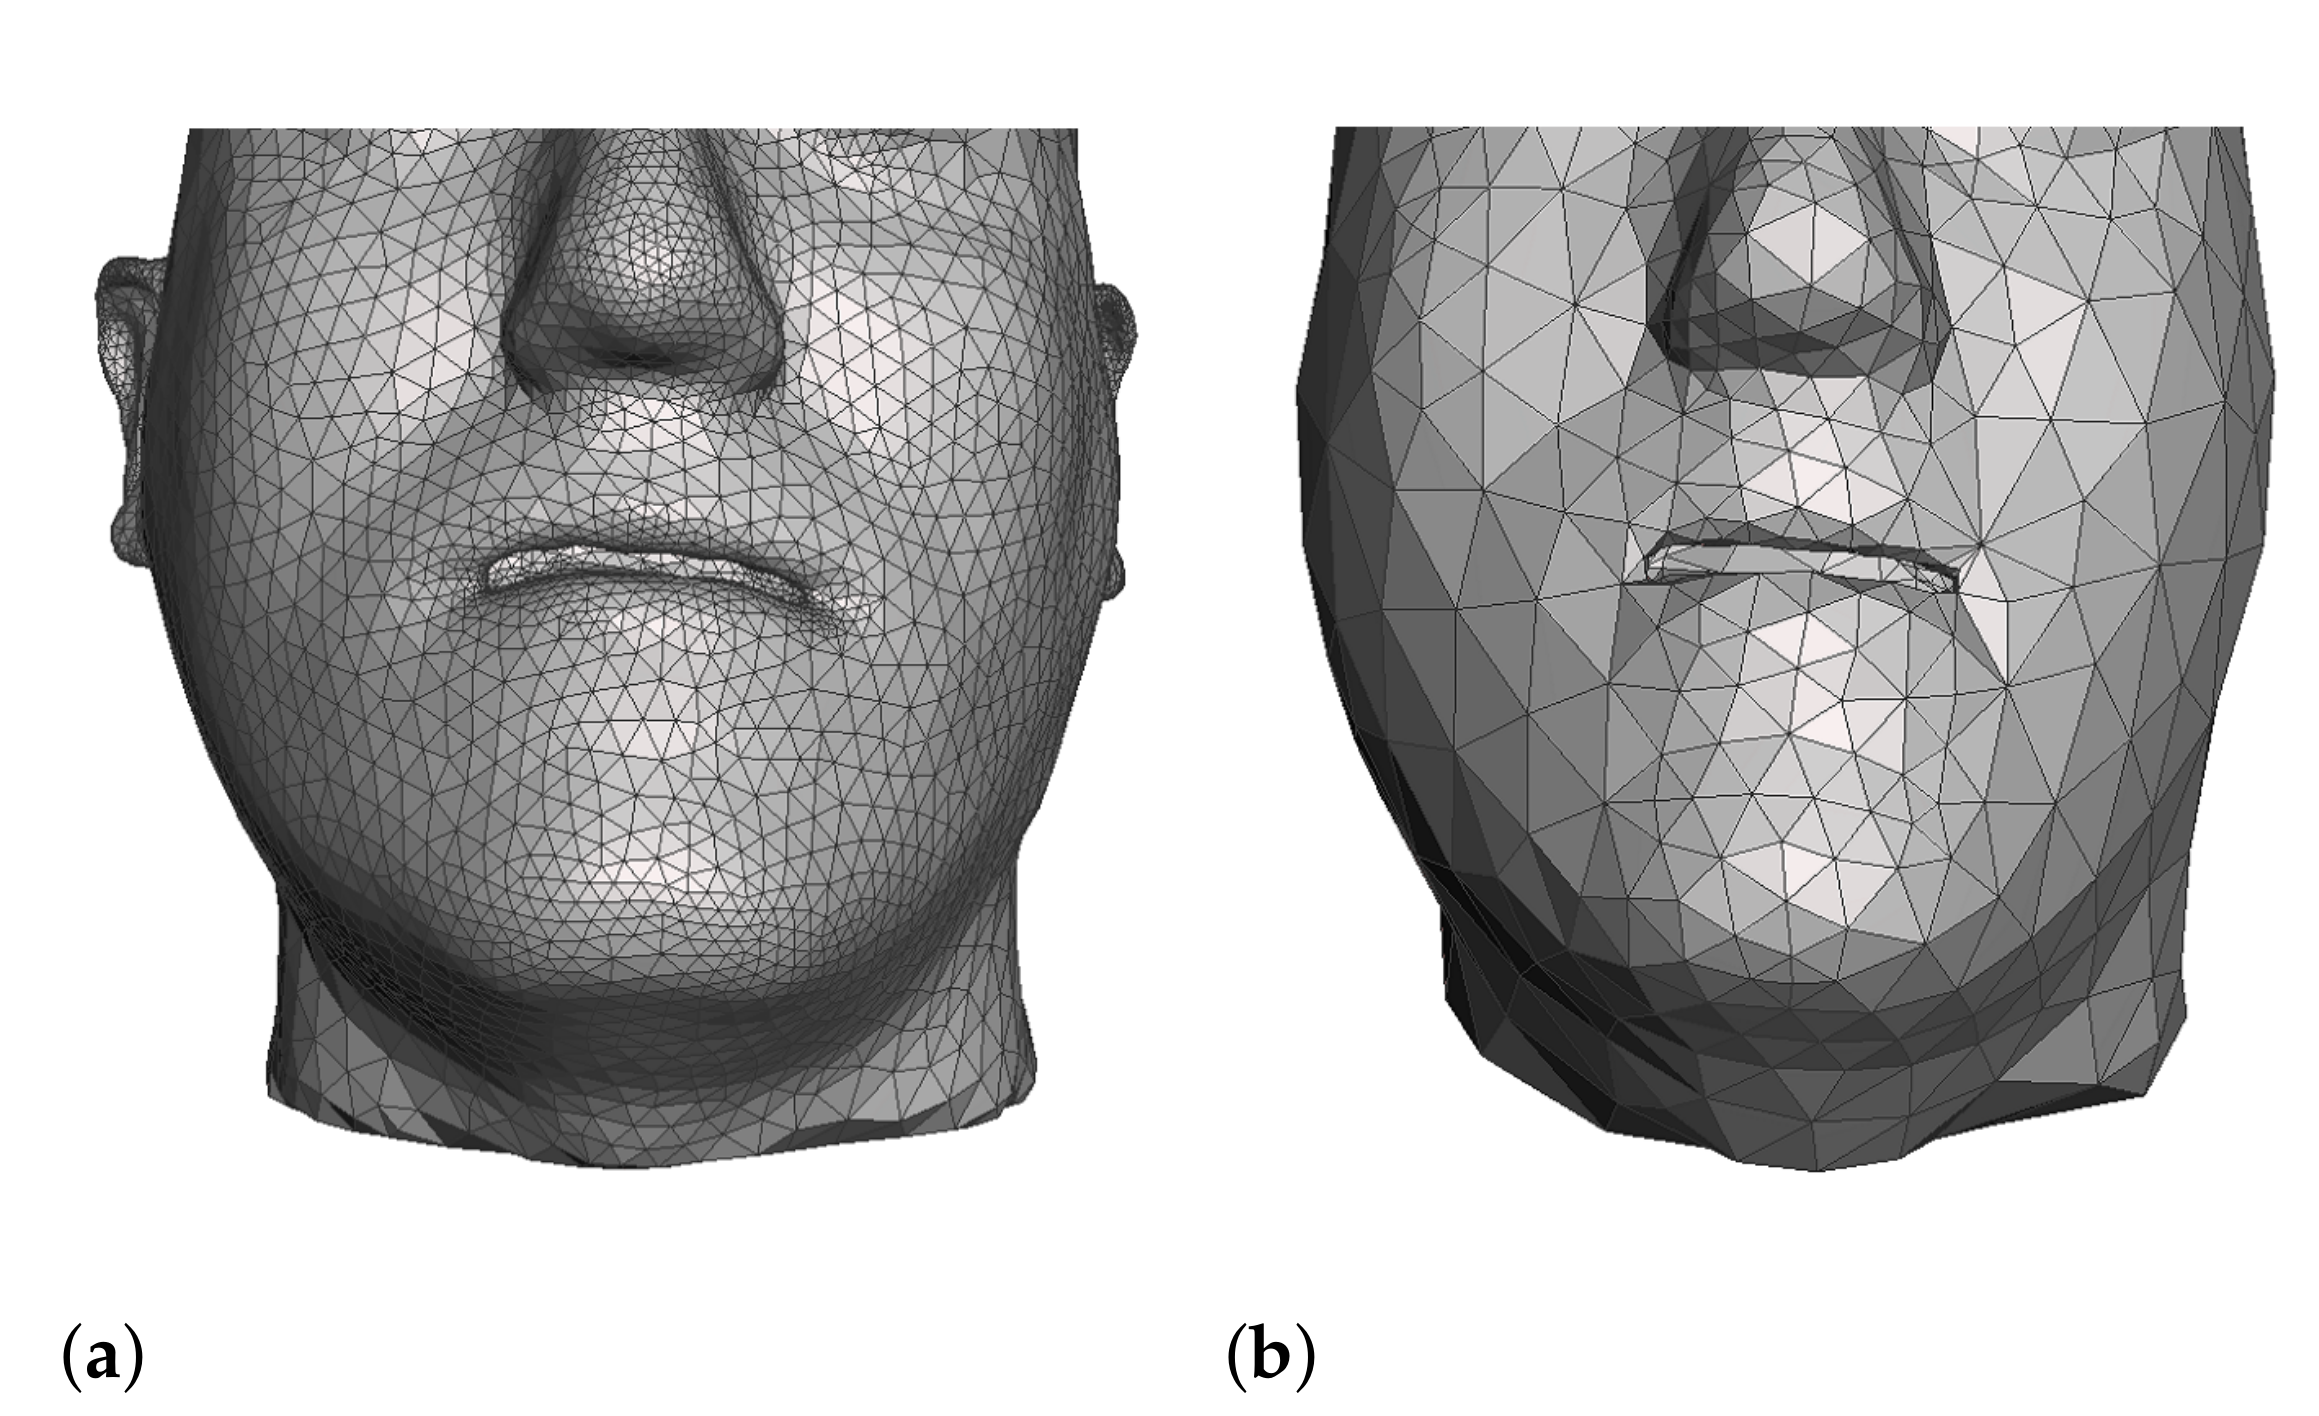

1.2.2. Simulation Meshes

4.3. Comparison of Fine and Coarse Meshes